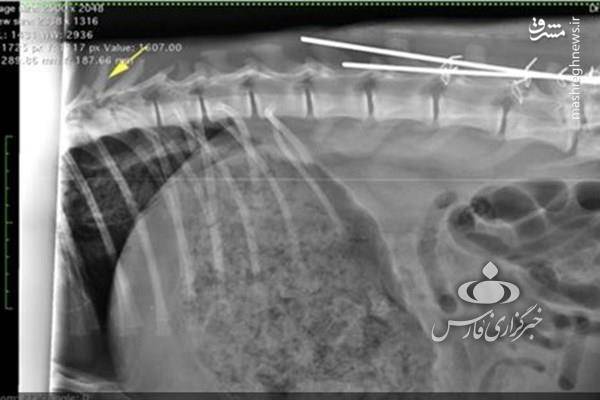

بنابر این گزارش که پس از انجام کالبد گشایی، پاتولوژی، سی ای اسکن و رادیولوژی تنظیم شده است دلایل مرگ یوزپلنگ سمنان به شرح زیر است:

- مهره L5 کمری شکسته و به شدت جابجا شده و مهره T8 سینه شکستگی و جابجایی کمی را نشان می دهد.

- عدم کارایی implant های قرار داده شده در جراحی که پس از آن تکه های کوچک بیشتری از مهره L5 شکسته است.

همچنین به دلیل عدم انجام اقدامات تشخیصی ازجمله سی تی اسکن و ام آر آی پیش از عمل جراحی، شکستگی مهره T8 و پارکی ریه در جانور تشخیص داده نشده و لذا اقدام درمانی خاصی نیز در این خصوص صورت نپذیرفته.